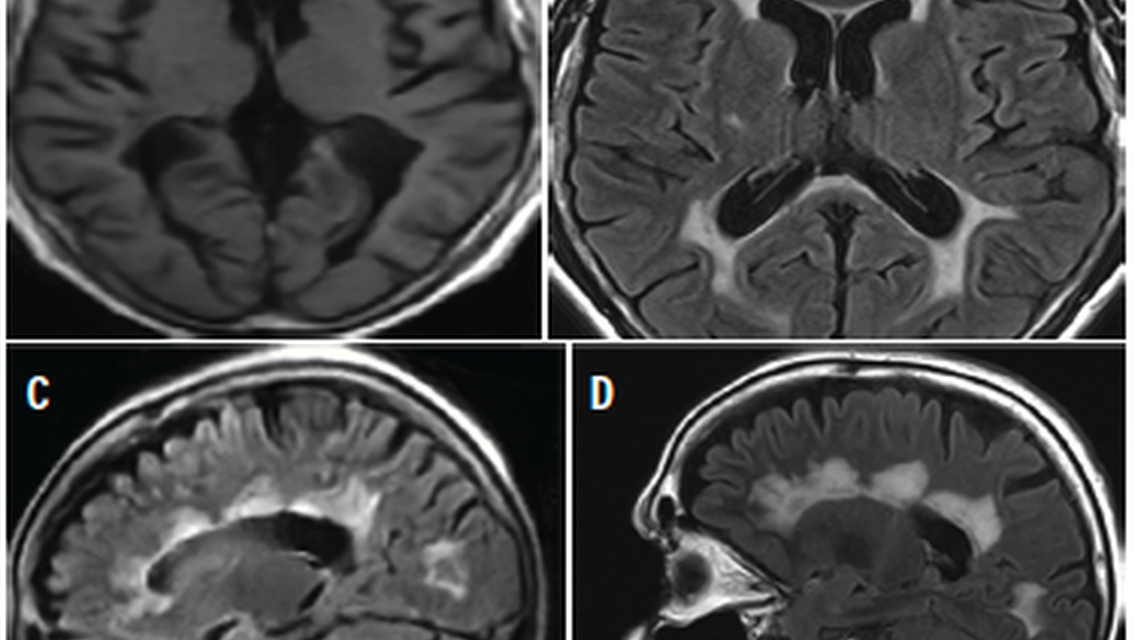

Figure 3. MRI scans from an individual, age early 60 years, with a 36-year history of chronic multiple sclerosis. Point-of-care axial T1-weighted (A) and fluid-attenuated inversion recovery (FLAIR) (B) images demonstrate cerebral atrophy, ex vacuo ventriculomegaly, and substantial periventricular white matter changes, consistent with the history of chronic MS. A point-of-care sagittal FLAIR image (C) is shown for comparison with a sagittal 3T FLAIR image (D).